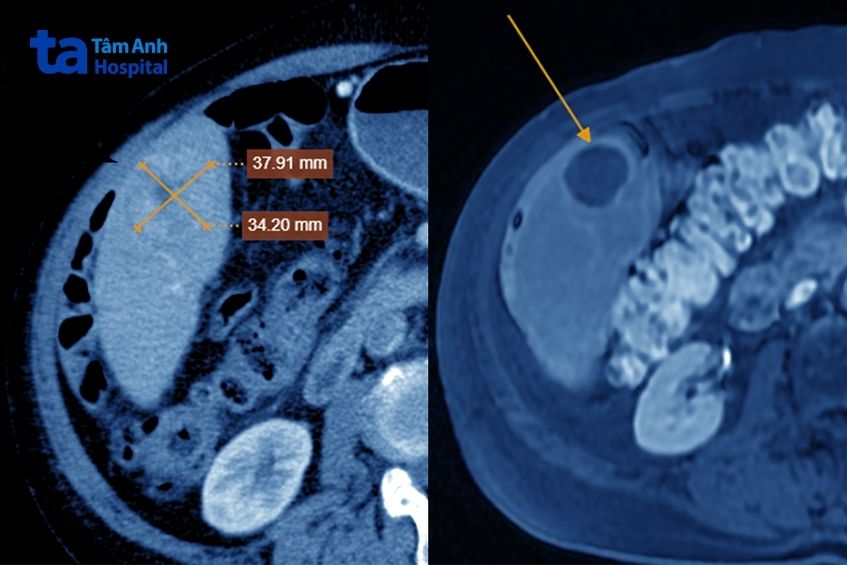

Chụp cắt lớp vi tính bằng máy CT Somatom Force VB 30 thấy hai khối u gan: kích thước 15×20 mm tại hạ phân thùy VIII và 37×34 mm tại hạ phân thùy VI, ngấm thuốc. Phim chụp còn phát hiện bệnh nhân có lóc tách động mạch chủ ngực, xơ vữa, phình, giãn một số động mạch chủ khác và hẹp 56% gốc động mạch thân tạng.